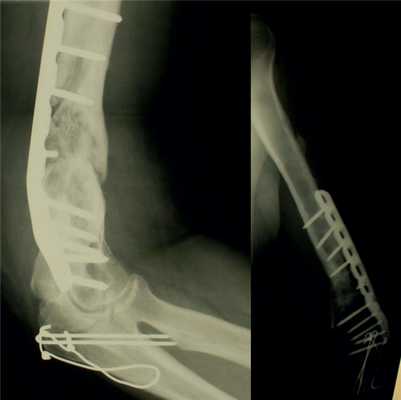

В отделении микрохирургии и травмы кисти ФГБУ «НМИЦ ТО им. Н.Н. Приорова» в период с 2010 по 2017 г. было проведено оперативное лечение 41 пациента (19 мужчин, 22 женщины) с ложными суставами и дефектами плечевой кости с использованием васкуляризованных костных трансплантатов. Средний возраст пациентов составил 41 год (18-65 лет), средний период времени с момента травмы — 2 года и 4 мес (1-8 лет).

До поступления в НМИЦ ТО им. Н.Н. Приорова некоторые пациенты уже были оперированы с применением различных методик наружного и погружного остеосинтеза: среднее количество операций — 2,2 (2-7).

Кровоснабжаемый трансплантат из малоберцовой кости использовался у 38 (93%) пациентов, васкуляризованный трансплантат из медиального мыщелка бедренной кости — у 3 (7%) пациентов (рис. 1). Рис. 1. Распределение пациентов по типу васкуляризованного трансплантата.

Во всех случаях применялся накостный остеосинтез пластиной без контакта пластины с трансплантатом (мостовидная костная пластика).

Консолидация перелома при кровоснабжаемой костной пластике была достигнута в 36 (88%) случаях в течение 4-6 мес (рис. 2): Рис. 2. Результаты оперативного лечения с использованием кровоснабжаемой костной пластикой. в группе применения малоберцового трансплантата консолидация была достигнута в 33 случаях, в группе трансплантата из мыщелка бедренной кости — в 3 случаях.

Васкуляризованный трансплантат из малоберцовой кости имеет преимущества в случае больших костных дефектов, при нестабильности и инфицированности ложного сустава, особенно при наличии множественных неудавшихся попыток получить сращение другими способами, при атрофии костной ткани и повреждении окружающих мягких тканей. Использование васкуляризованного трансплантата из малоберцовой кости, как правило, приводит к заживлению перелома с хорошим восстановлением мягких тканей и разрешением хронической инфекции [15].

Заключение. Таким образом, при длительно существующих посттравматических ложных суставах и дефектах плечевой кости, при наличии двух и более оперативных вмешательств с неудовлетворительным результатом в анамнезе кровоснабжаемая костная пластика является эффективным способом лечения.